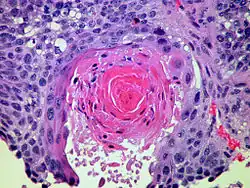

Plattenepithelkarzinom

Das Plattenepithelkarzinom ist mit ca. 40 bis 45 Prozent[25] der häufigste nichtkleinzellige Bronchialtumor. Er entsteht nach chronischer Schleimhautreizung über die Plattenepithelmetaplasie aus einer Plattenepitheldysplasie. Häufig ist er an den Aufzweigungen der Subsegmentbronchien lokalisiert. Charakteristisch sind sein langsames Wachstum und seine frühe Metastasierung in die regionären Lymphknoten. Makroskopisch sind Ulzerationen, Nekrosen, Blutungen und pseudozystische Umwandlung bei diesem grauweißlichen Tumor häufig. Histologisch unterscheidet man in einen verhornenden Typ und in einen nichtverhornenden Typ. Letzterer bringt auf Grund seiner geringeren Differenzierung eine schlechtere Prognose mit sich. Die Fünfjahresüberlebensrate beträgt je nach Stadium (TNM; AJCC) zwischen 20 und 1 %.

Histologisch sieht man bei gut differenzierten Tumoren an Plattenepithel erinnernde geschichtete Tumorzellverbände aus mittelgroßen bis großen Tumorzellen mit breitem eosinophilen Zytoplasma, eher hellen Zellkernen mit großen Nukleolen und ggf. charakteristische Interzellularbrücken und Verhornungszeichen mit Ausbildung von „Hornperlen“. Dysplasien bis hin zum Carcinoma in situ im Bronchusepithel sprechen für eine in der Lunge selbst entstandene Läsion. Ansonsten müssen (insbesondere bei fehlenden Risikofaktoren wie z. B. Rauchen, Asbestexposition, Z.n. Radio-/Chemotherapie oder chronischen Lungenerkrankungen) differentialdiagnostisch auch Metastasen von Plattenepithelkarzinomen anderer Lokalisation, z. B. aus dem HNO-Trakt, der Haut oder der Cervix uteri, in Betracht gezogen werden. Drüsige Strukturen und Schleimbildung sollten nicht zu sehen sein bzw. an ein Adenokarzinom denken lassen. Bei schlecht differenzierten Tumoren kann die Einordnung schwierig sein. Hierbei kann die Immunhistochemie helfen. Plattenepithelkarzinome sind meist positiv für Plattenepithelmarker wie CK5/6 und p63 und negativ für CK7. TTF1 ist eher selten nachweisbar. Die Wachstumsrate (Ki-67) ist deutlich erhöht, aber nicht so stark wie beim SCLC.